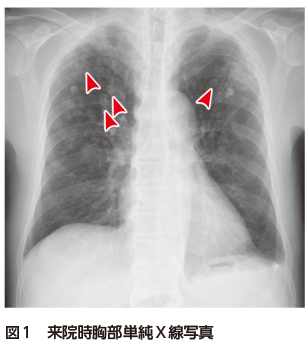

本症例では,胸部CTにおいて散在性に結節影を認め,多くは内部に三日月状の透亮像を伴っていた(図2).血液検査ではβ-Dグルカン141.9 pg/mL,アスペルギルス抗原4.7(陽性)であり,IPAを疑い気管支鏡検査を施行した.気管支洗浄液培養でAspergillus fumigatusが同定され,病理組織学的には壊死に陥った気管支軟骨の周囲や内部に真菌が取り囲むように増殖している所見を認めた(図3).以上よりIPAと診断した.

図3